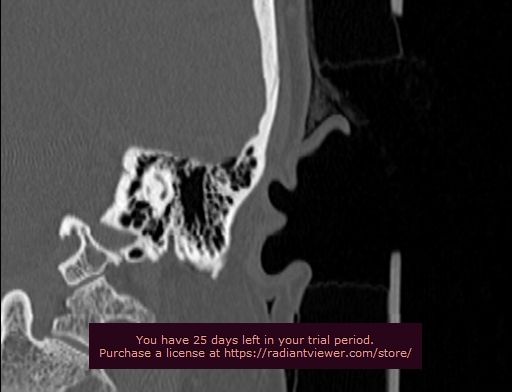

Женщина лет 50, беспокоит дискомфорт слева в заушной области. От левого поперечного отростка С1 позвонка есть костный выступ упирающийся в затылочную кость с формированием ямки как бы в виде...

Тип: Клиническое наблюдение

Область: Череп и головной мозг, Скелетно-мышечная система

Модальность: КТ

Дата: 20.07.2022 - 19:15